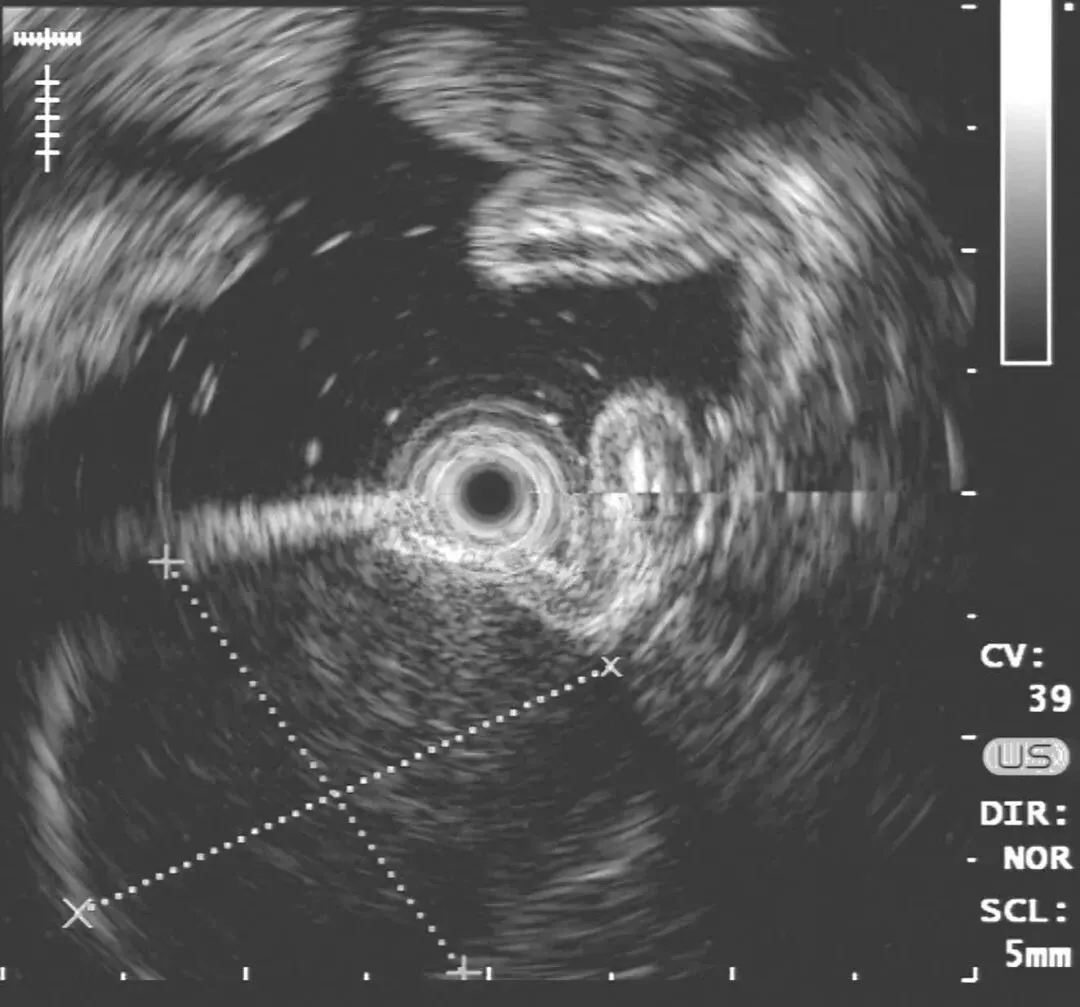

超声胃镜:胃体上段后壁可见一隆起病灶,隆起处为一低回声团块,内回声尚均匀,起源于第四层,向腔内外突出(图2-1)